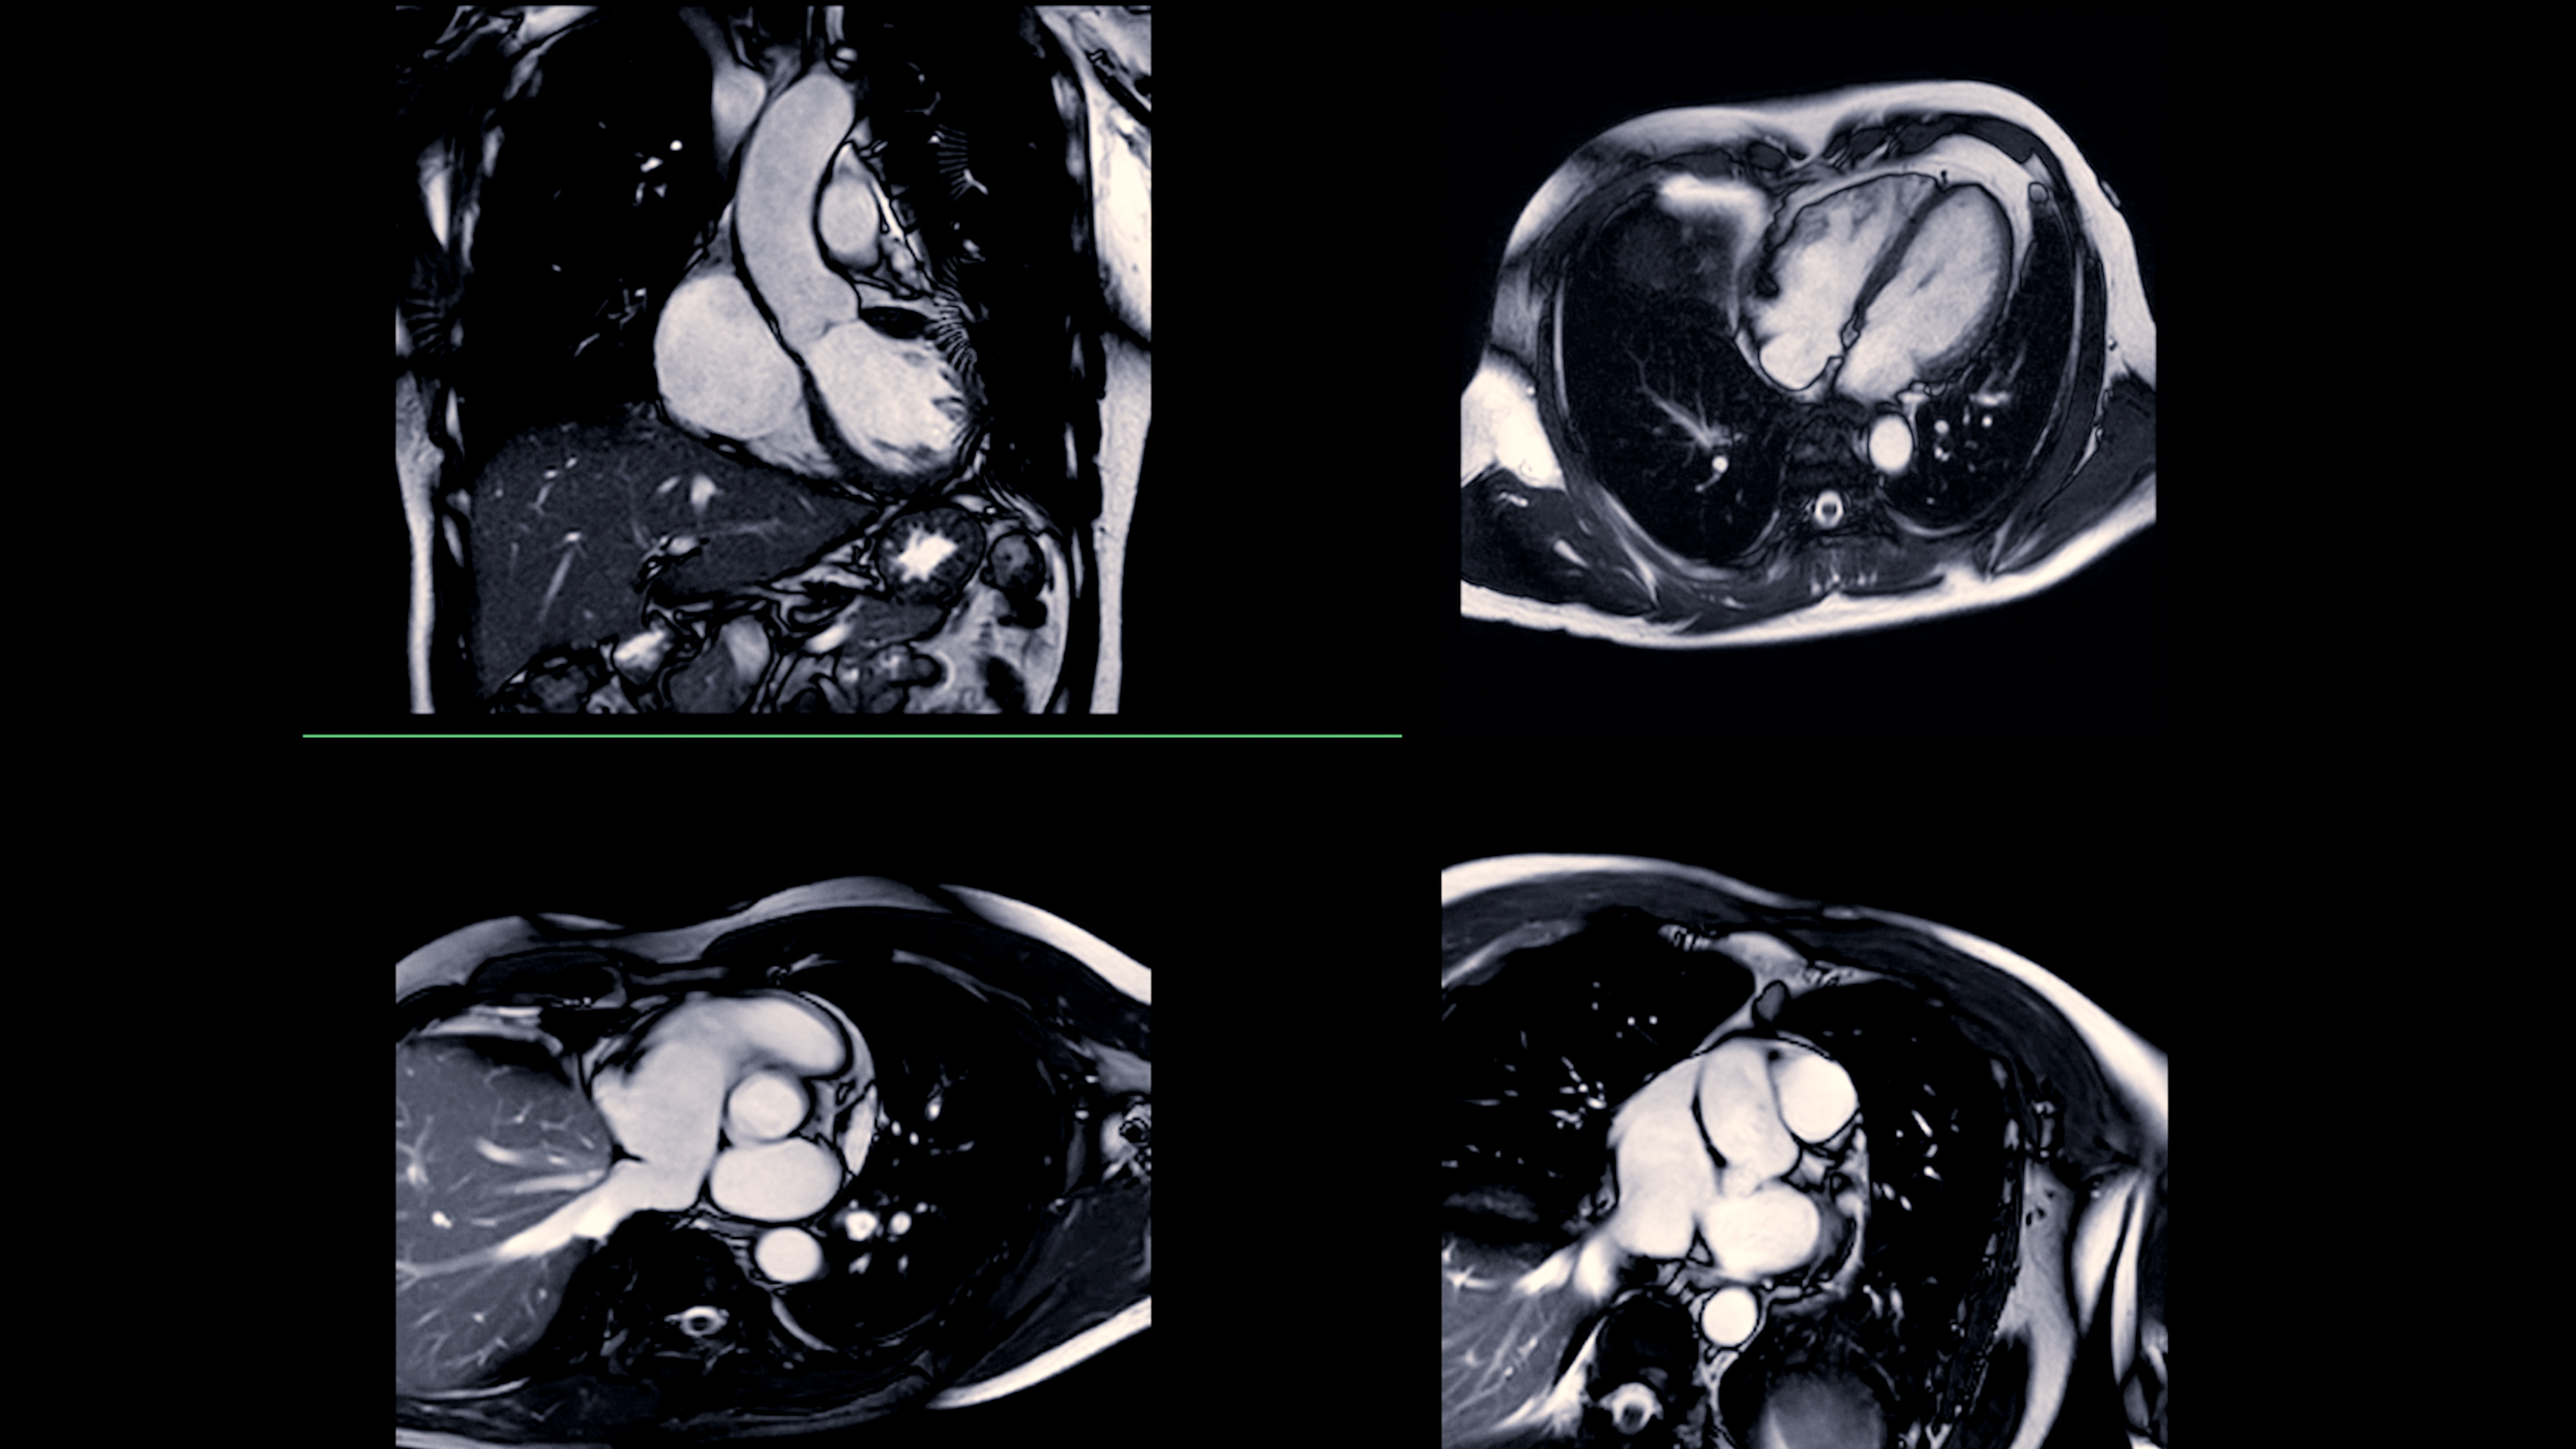

Diffusion-tensor images were acquired on a 3-tesla MR scanner (Philips Healthcare). In all, 56 measures were obtained to test the relationship between oxidative stress and axial diffusivity, radial diffusivity, fractional anisotropy, and mean diffusivity. In addition, the International Consortium for Brain Mapping (ICBM) DTI-81 white-matter atlas was used to label brain regions that showed significant differences between the cocaine users and the healthy controls.

The most significant differences between the two groups were in axial diffusivity measurements (p < 0.05) in the anterior (or knee) of the corpus callosum, the body of the corpus callosum, the left superior corona radiata, and the left anterior corona radiata. The axial diffusivity values within these white-matter regions also correlated significantly (p < 0.05) with several oxidative stress measures. The researchers found no significant differences between the groups for fractional anisotropy, mean diffusivity, and radial diffusivity.

Axial view of white-matter tracts in the brain. Computer analysis was used to determine statistically significant differences between those with cocaine use disorder and healthy subjects. Image courtesy of Abbey Goodyear."These findings strengthen the use of axial diffusivity as a measure of white-matter change proposed as axonal fragmentation and decreased connectivity, provide new insight into peripheral markers of neuronal damage in specific brain regions associated with cocaine use disorder, and provide further evidence for the oxidative stress theory of cocaine use disorder associated microstructural change," Goodyear said.